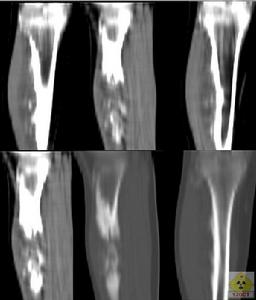

3.CT檢查:能清晰的顯示出腫瘤與受累骨皮質和松質骨相連,軟骨帽部分呈軟組織密度,有時可見不規則的鈣化及骨化。

4.MRI檢查:骨性部分的信號與相鄰乾骺端松質骨的信號相同,軟骨帽在T1加權像上呈低信號,T2加權像上呈高信號。MRI檢查可以明確軟骨帽的厚度,如超過25mm者應考慮有惡變可能。